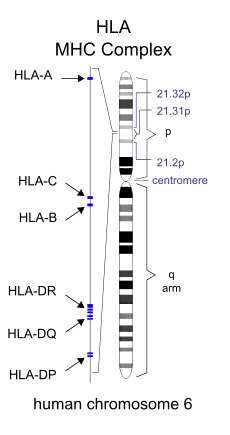

The major histocompatibility complex (MHC) is a large genomic region found in most vertebrates that is associated with the immune system. It is located on chromosome 6 in humans. A subset of MHC in humans is human leukocyte antigen (HLA), which controls the antigen-presenting system, as part of adaptive immunity against pathogens such as bacteria and viruses. When human cells are infected by a pathogen, some of them can present parts of the pathogen's proteins on their surfaces; this is called "antigen presentation". The infected cells then become targets for types of cytotoxic T-cells, which kill the infected cells so they can be removed from the body.[8]

Genetic predisposition for DPB susceptibility has been localized to two HLA haplotypes (a nucleotide or gene sequence difference between paired chromosomes, that is more likely to occur among a common ethnicity or trait) common to people of East Asian descent. HLA-B54 is associated with DPB in the Japanese, while HLA-A11 is associated with the disease in Koreans.[9] Several genes within this region of class I HLA are believed to be responsible for DPB, by allowing increased susceptibility to the disease.[7][10] The common genetic background and similarities in the HLA profile of affected Japanese and Korean individuals were considered in the search for a DPB gene.[10] It was suggested that a mutation of a suspected disease-susceptibility gene located somewhere between HLA-B[11] and HLA-A[12] had occurred on an ancestral chromosome carrying both HLA-B54 and HLA-A11. Further, it is possible that a number of genetic recombination events around the disease locus (location on a chromosome) could have resulted in the disease being associated with HLA-B54 in the Japanese and HLA-A11 in Koreans. After further study, it was concluded that a DPB susceptibility gene is located near the HLA-B locus at chromosome 6p21.3. Within this area, the search for a genetic cause of the disease has continued.[9][10]

Because many genes belonging to HLA remain unidentified, positional cloning (a method used to identify a specific gene, when only its location on a chromosome is known) has been used to determine that a mucin-like gene is associated with DPB. In addition, diseases caused by identified HLA genes in the DPB-susceptibility region have been investigated. One of these, bare lymphocyte syndrome I (BLS I), exhibits a number of similarities with DPB in those affected, including chronic sinusitis, bronchiolar inflammation and nodules, and the presence of H. influenzae. Also like DPB, BLS I responds favorably to erythromycin therapy by showing a resolution of symptoms. The similarities between these two diseases, the corresponding success with the same mode of treatment, and the fact that the gene responsible for BLS I is located within the DPB-causing area of HLA narrows the establishment of a gene responsible for DPB.[9] Environmental factors such as inhaling toxic fumes and cigarette smoking are not believed to play a role in DPB, and unknown environmental and other non-genetic causes—such as unidentified bacteria or viruses—have not been ruled out.[4][6][7]